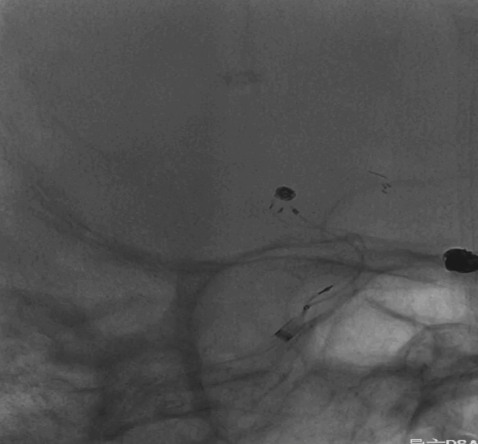

术前外院 DSA 2025-02

箭头所指右侧A1微小动脉瘤

工作位正位造影(图片)

工作位侧位造影(图片)